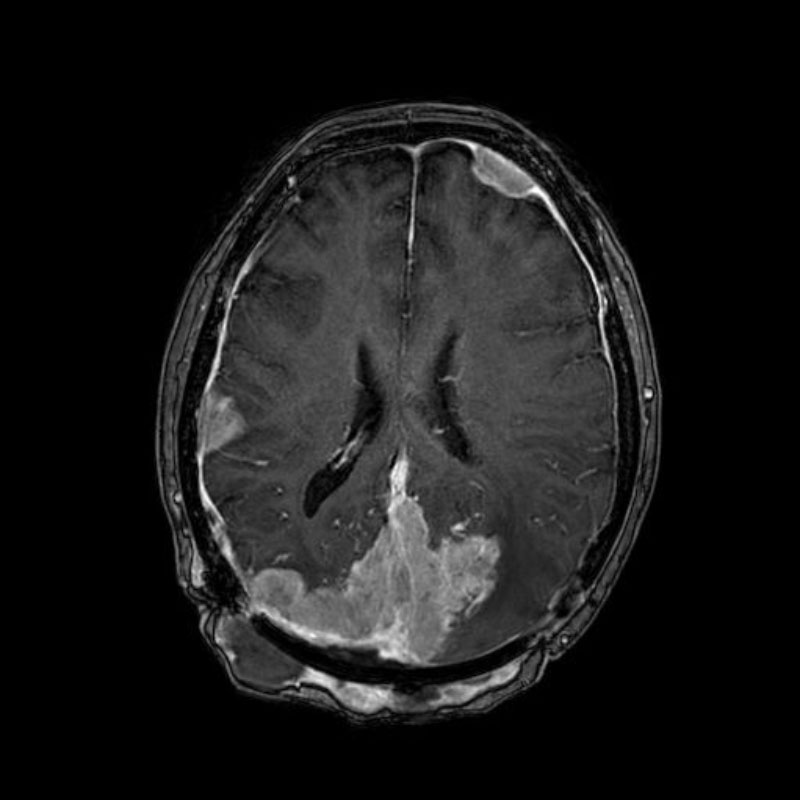

No.’25_108 摘出 前

No.’25_108  摘出 中